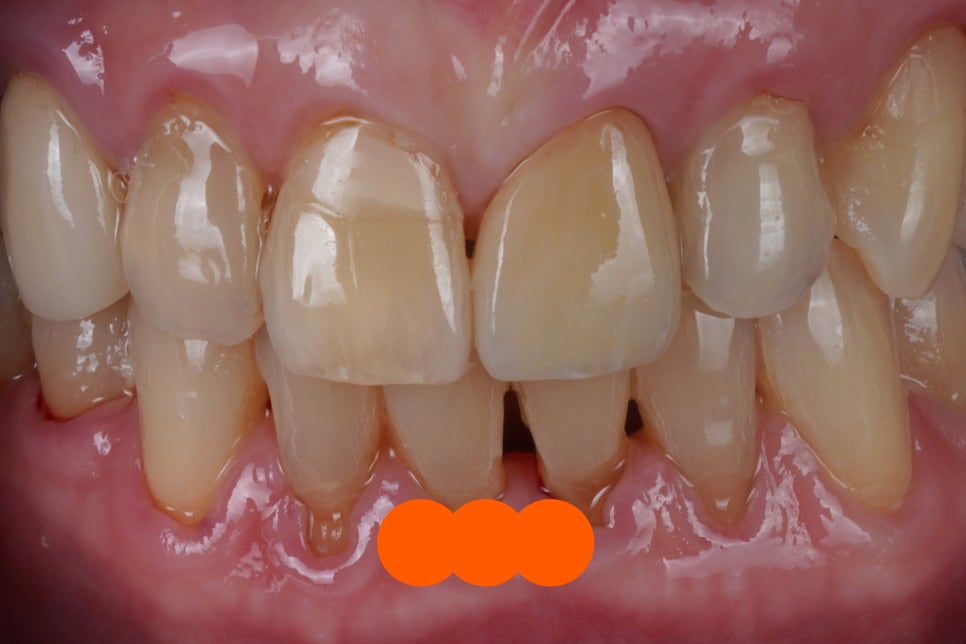

치료 완료

이 사진은 치료가 완료된 사진인데요

어떤 치아를 치료한 것인지

바로 한 번 알아볼게요.

다행히 지르코니아 크라운이 잘 만들어져서

자연치아와 구분이 힘들 정도로

잘 치료가 완료되었어요 :-)

정말 감쪽같죠?